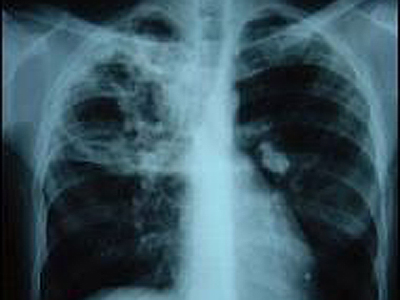

România continuă să înregistreze cele mai multe cazuri de tuberculoză dintre toate statele din Uniunea Europeană. Raportările din perioada pandemiei indică o reducere cu aproape o treime, însă scăderea este posibil să fie doar un efect al lipsei depistării şi al reticenţei de a merge la medic – o spun chiar specialiştii. Pentru a descoperi din timp cazurile de tuberculoză şi a putea fi tratate, Ministerul Sănătăţii a lansat un program prin care medicii ajung în 11 judeţe, la persoanele de peste 18 ani cu factori de risc pentru această boală. Echipele mobile au ajuns în judeţul Vaslui, iar directorul DSP, Mihaela Vlada, subliniază că, în cadrul programului, poate fi testată orice persoană, indiferent de statutul de asigurat:

Pentru programul de depistare a tuberculozei, din judeţul Vaslui au fost selectate, până acum 5 localităţi din mediul urban şi 9 din mediul rural.